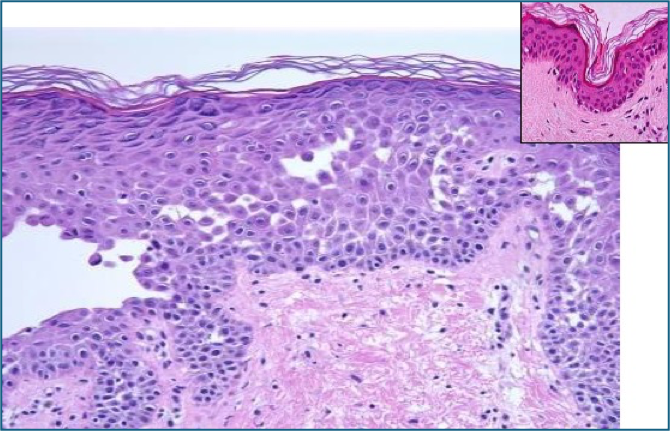

Acantholysis

- = Loss of intercellular desmosomal attachments between keratinocytes

- ➝ Leads to intraepidermal blistering

- Mechanism: Autoimmune attack (commonly against desmoglein)

- Seen in: Pemphigus vulgaris